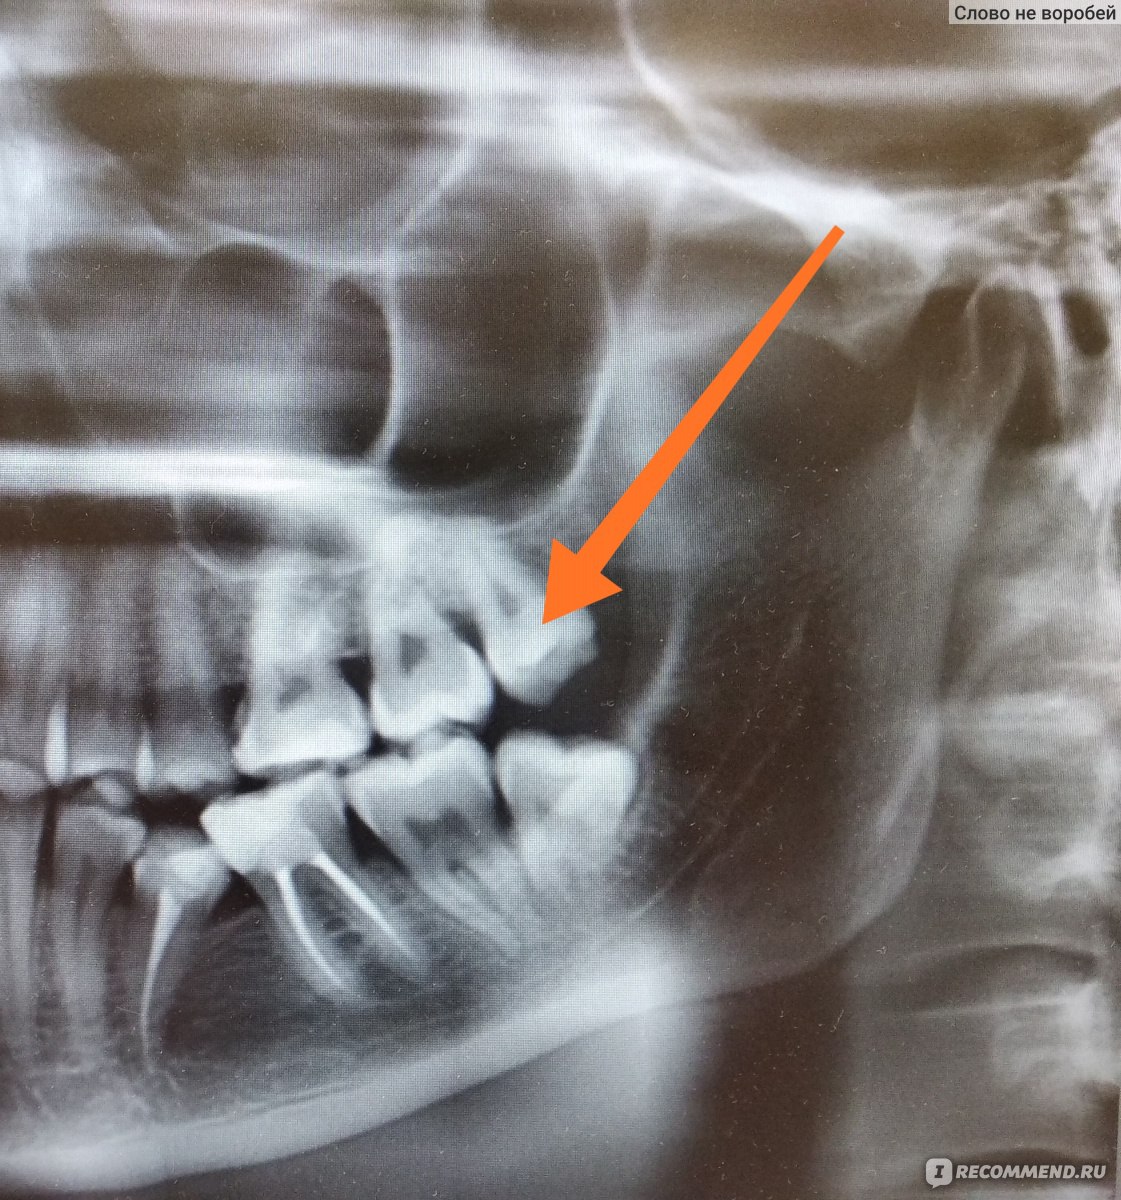

Дентальная галерея: ретинированный зуб клык и его лечение

Раздел: Компас решений